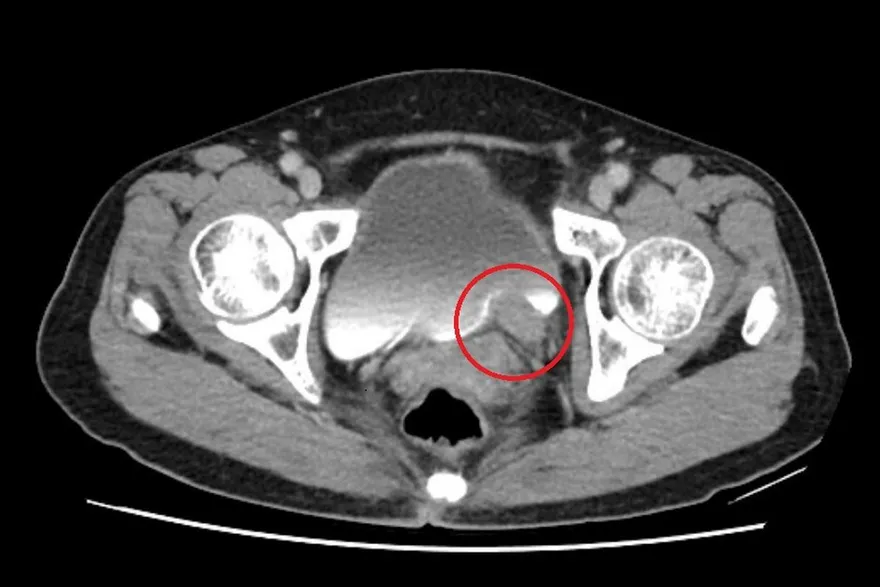

巧克力囊腫

子宮內膜異位

卵巢囊腫

子宮內膜異位症